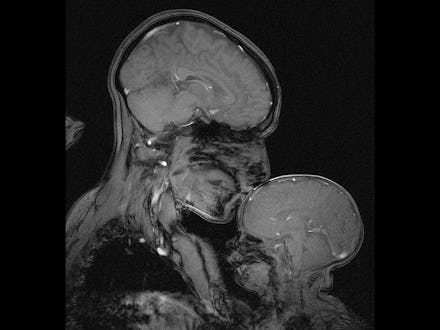

This Brain Scan Image Illustrates the Powerful Bond Between Mother and Child

While most new moms get their children's first portrait done at, say, the local mall's JC Penney Portrait Studio, neuroscientist Rebecca Saxe opted for a slightly different location: the tube of an MRI scanner.

"No one, to my knowledge, had ever made an MR image of a mother and child," she wrote in a article for Smithsonian magazine.

"We see brain scan images on TV and in subways advertisements as a proxy for technology and progress... [and] the Madonna is one of the oldest tropes in human art making," she said of trying to capture the union between science and art in the image.

"These brain scanners are extremely modern technology, only available here and now, to the wealthiest place and time in human history," she added. "[Yet] the image you see would look the same if it had been made on any continent or in any century, because the biology of human mothers and children you see in the picture has been the same for thousands, probably tens of thousands of years."

In an interview with Today, Saxe suggested that the image may be indicative of how a child's brain development is strengthened by a mother's love. "Some people look at it and see mostly the differences: how thin his skull is, how little space there is between the outside world and his brain. It's just this very fragile, very thin little shell," she said. "On the other hand, you can look at it and see how similar it is to his mother's brain. How close in size — so much closer in size than his hand is."